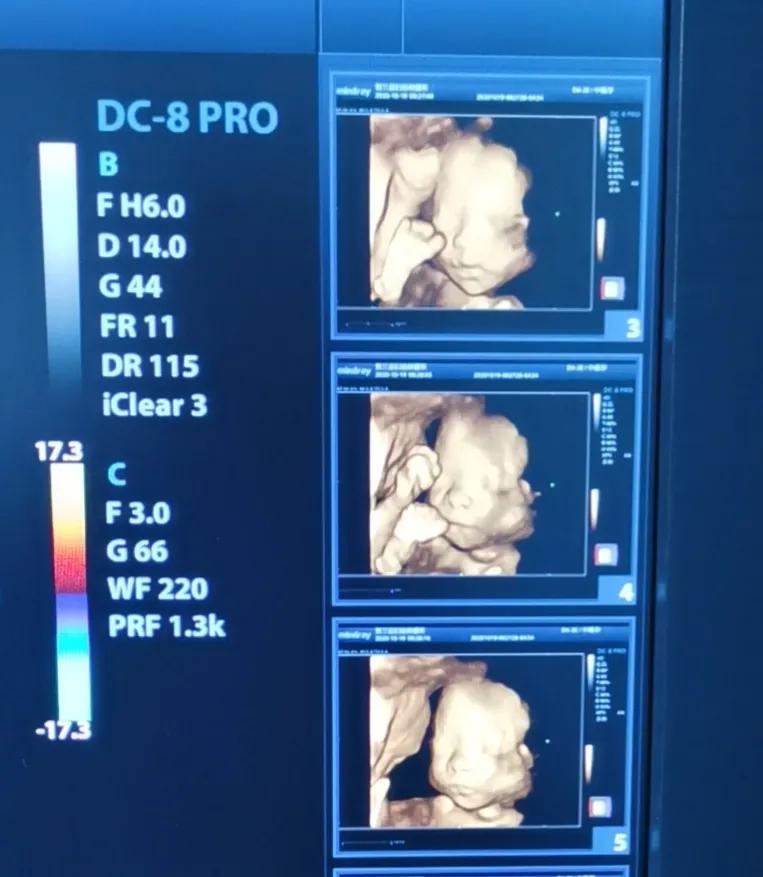

四维彩超,正在啃脚丫的大犇